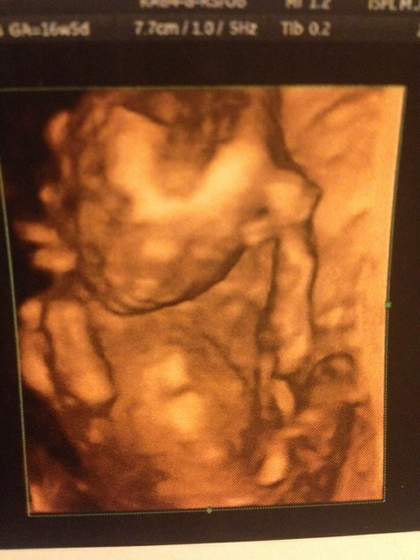

Melduje sie po wizycie. U mnie i u SYNKA wszystko ok :)

Maluszek jest juz na tyle duzy ze cieżko było go zmierzyć, wiem tylko tyle ze ma juz ponad 10 cm i wazy ok 170 gramów :)

Serduszko obejrzane i wyglada wspaniale, ale niedługo idziemy jeszcze na echo zeby miec pewność.

FHR 155 bpm. Żołądek, wątroba, pecherz - wszystko na swoim miejscu.

Moja szyjka długa i zamknieta, 44 mm. Lozysko na tylnej ścianie.

A to mój mały miś: